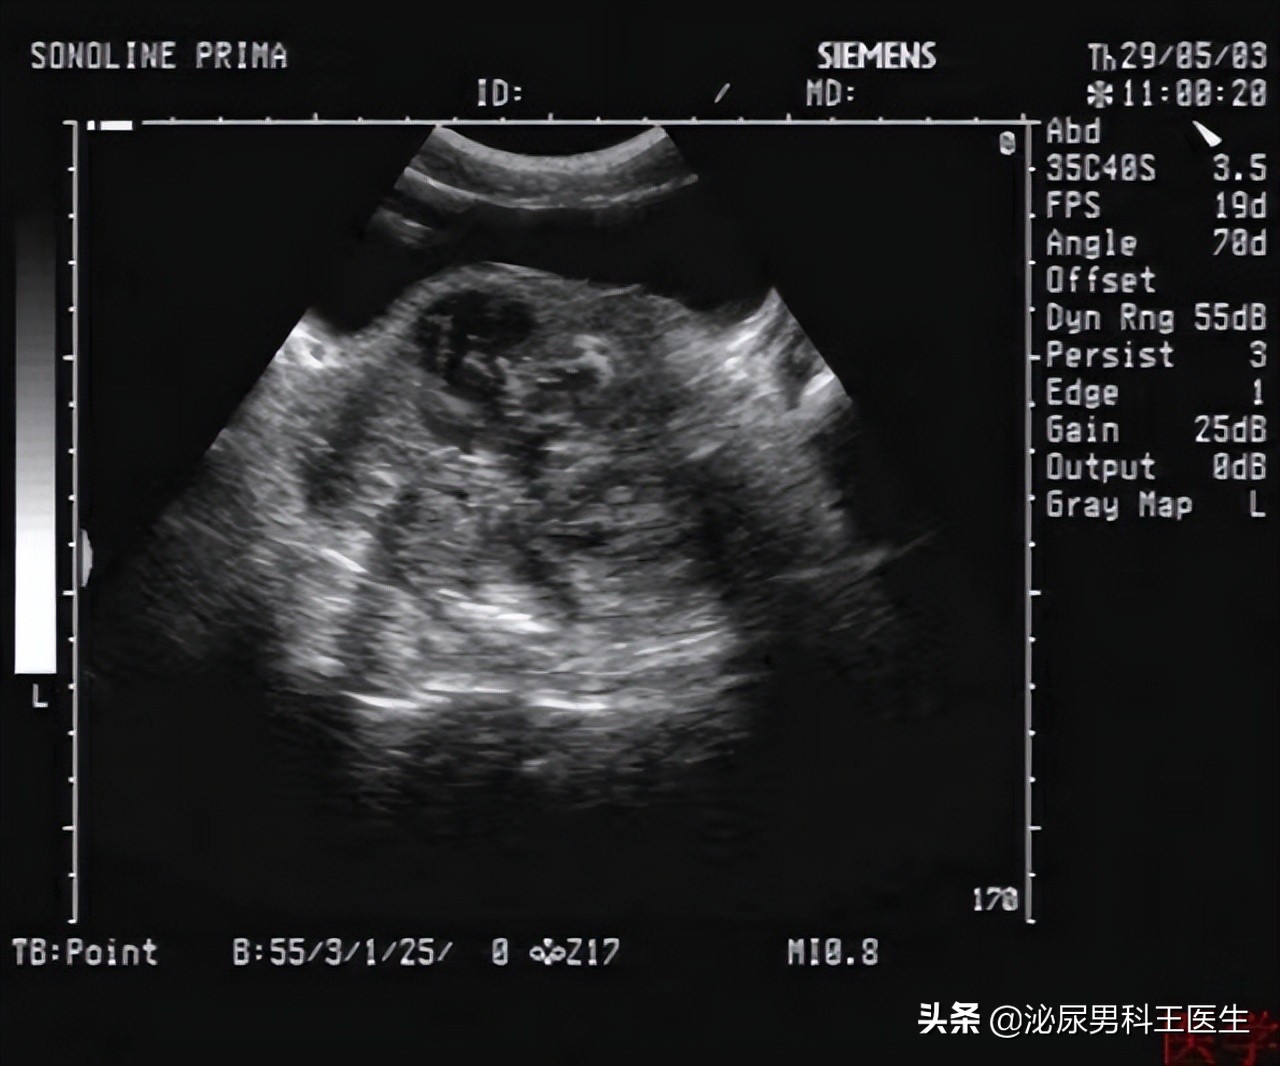

还有用 影像学的检查 ,包括直肠超声检查,磁共振,CT等等。